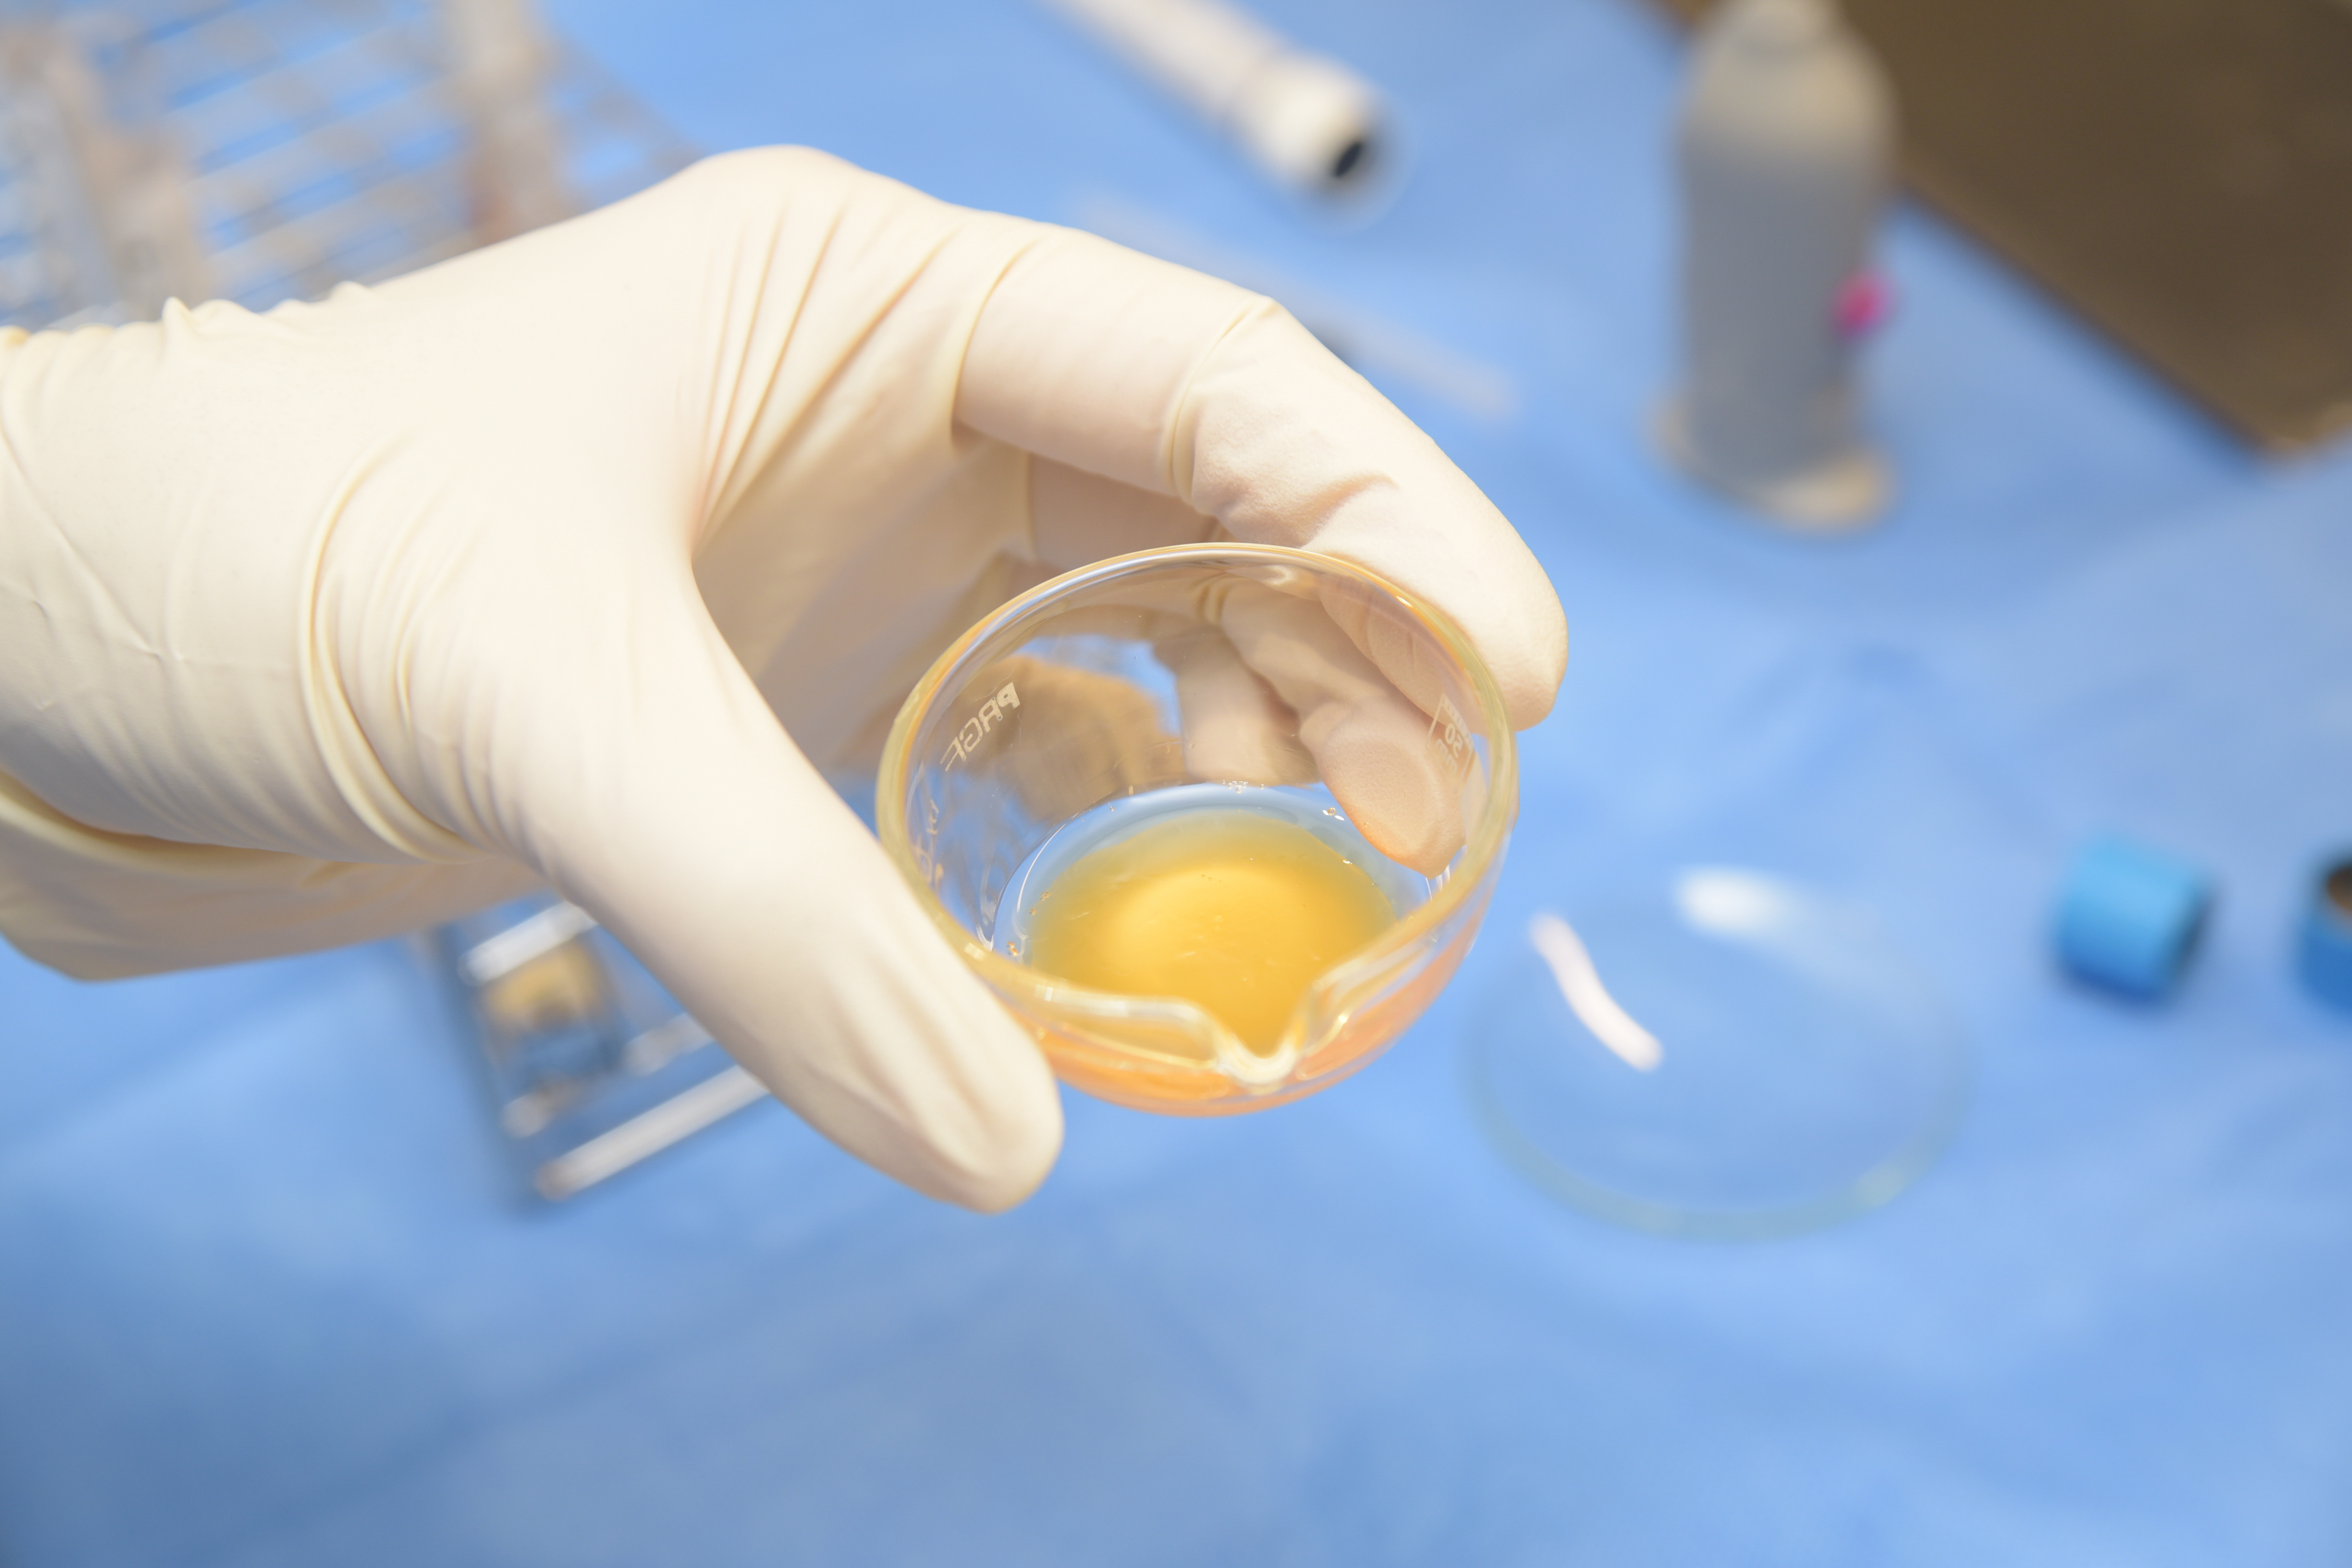

CGF(Concentrated Growth Factors)療法は、患者さんご自身の血液に含まれる「成長因子」の力を利用し、失われた骨や歯ぐきの再生を促す再生医療です。

まず患者さんの血液を採取し、専用の遠心分離機で処理して成長因子を高濃度に含んだCGFを生成します。これを患部に注入することで、ダメージを受けた組織の修復と再生が促進されます。

最大の特徴は、ご自身の血液から作るため、アレルギーや拒絶反応の心配がほとんどないこと。身体に優しく、自然の治癒力を最大限に活かせる、安全性の高い治療法です。